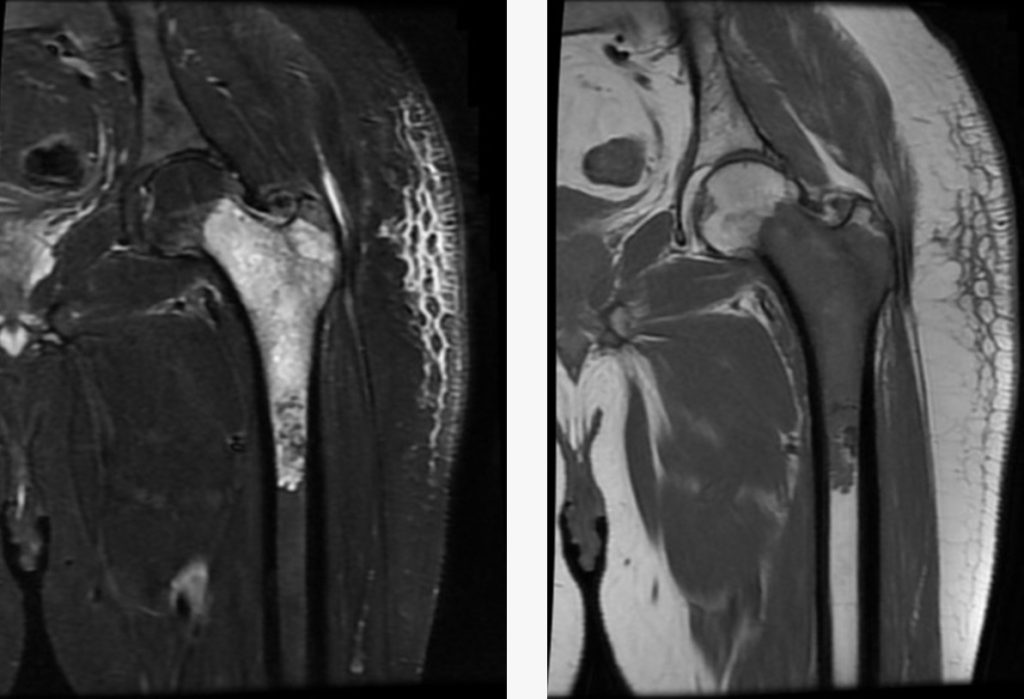

Malignant bone tumors, also known as primary bone cancers, are aggressive cancers that originate in bone tissue itself. The most common types include osteosarcoma (typically in teenagers around the knee), Ewing sarcoma (often in children and young adults affecting pelvis or long bones), and chondrosarcoma (more common in adults, arising from cartilage).

Dr. Pradeep Kumar, with advanced fellowship training in Musculoskeletal Oncology from Tata Memorial Centre, specializes in precise diagnosis using multimodal imaging (X-ray, MRI, PET-CT) and biopsy to confirm malignancy and subtype.